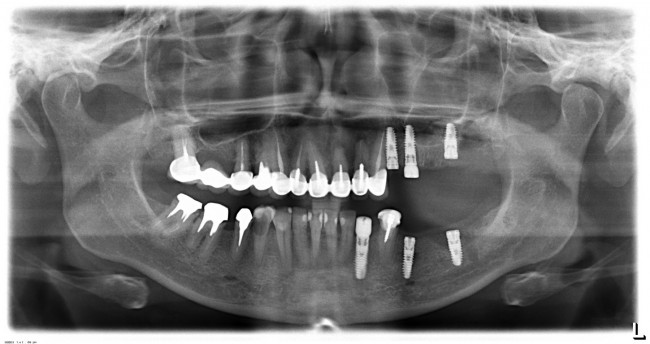

Вот пример. На этот раз, на снимках: пациентка, возрастом чуть больше сорока лет. После диагностики и необходимых исследований стало ясно, что необходимо хирургическое лечение во всех участках зубного ряда. В частности, удаление 13 зубов, включая ретинированный зуб мудрости, остеопластика на нижней челюсти и синуслифтинг, пластика слизистой и много чего еще.

Представьте, сколько времени займет хирургическая операция, если делать хотя бы половину этой работы за один раз? Как себя будет чувствовать пациентка во время и после хирургической операции? Как будет себя чувствовать доктор, какова вероятность критической усталости к концу операции? Как поддерживать анестезию и чистоту полости рта в течение такого длительного времени? И сколько будет стоить такая операция?

У меня нет ипотеки и других долгов, поэтому я принимаю решение разбить весь объем хирургического лечения на четыре этапа — по одному в каждом из сегментов зубного ряда. И начинаю я… угадайте, с какого участка? Верно, с того, который уже не функционален из-за критического разрушения зубов — с левого нижнего:

Операция заняла всего 60 минут, послеоперационные явления были настолько незначительны, что пациентка чуть ли не через пару недель решилась на вторую операцию: